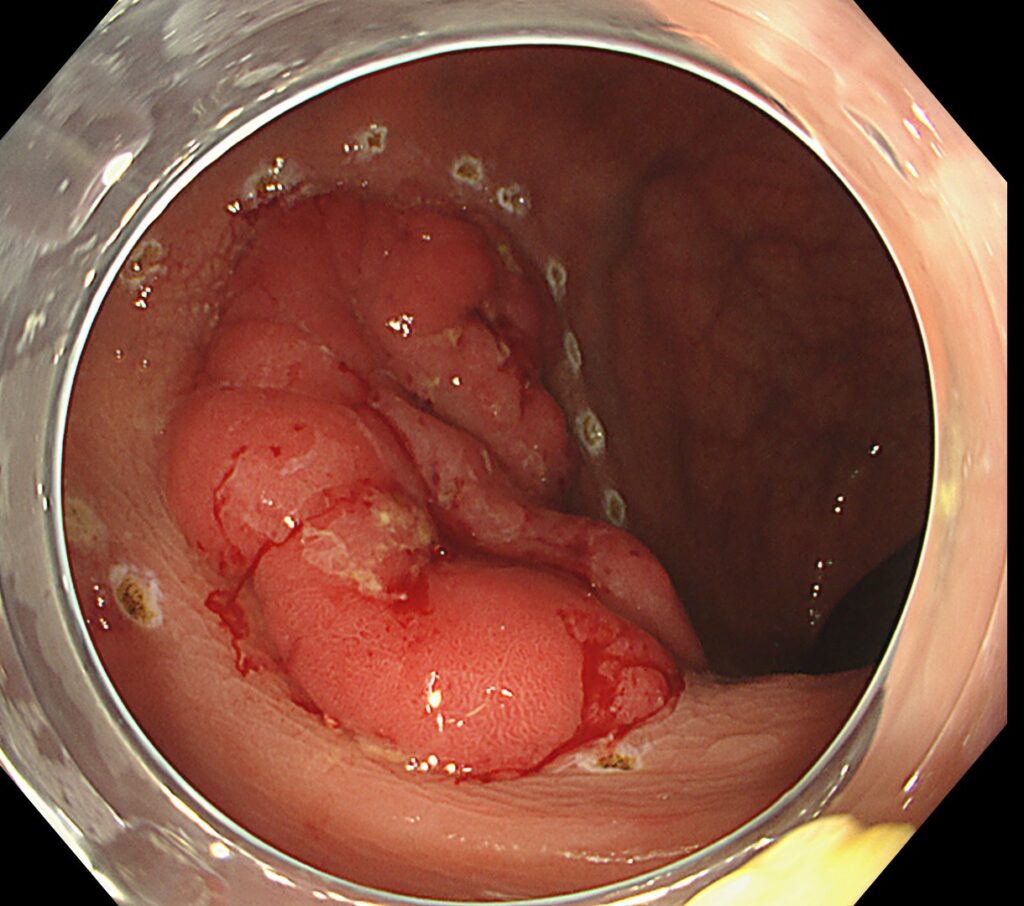

肛門から内視鏡を入れてすぐの下部直腸に、隆起性病変を認めます。

送気・脱気で腫瘍の硬さを確認してみると、浸潤癌らしき所見は認めず。

しっかり、空気を入れて、全体像を確認すると、内腔を1/4占めていることがわかります。